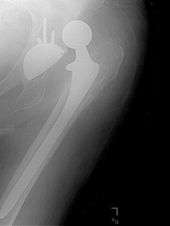

Hip replacement is a surgical procedure in which the hip joint is replaced by a prosthetic implant. Hip replacement surgery can be performed as a total replacement or a hemi (half) replacement. Such joint replacement orthopaedic surgery is generally conducted to relieve arthritis pain or in some hip fractures. A total hip replacement (total hip arthroplasty) consists of replacing both the acetabulum and the femoral head while hemiarthroplasty generally only replaces the femoral head. Hip replacement is currently the most common orthopaedic operation, though patient satisfaction short- and long-term varies widely. The average cost of a total hip replacement in 2012 was $40,364 in the United States, and about $7,700 to $12,000 in most European countries.[1]